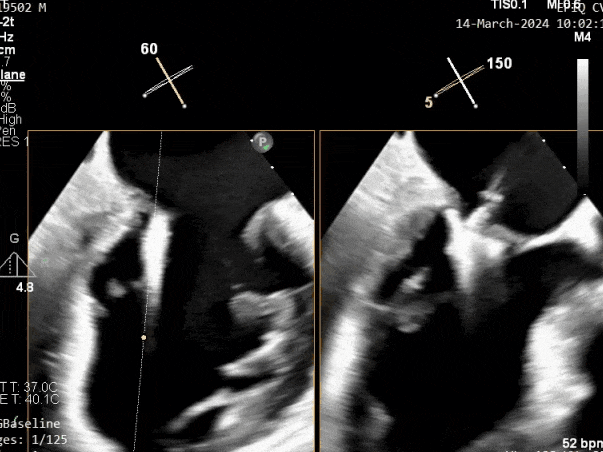

超声心动图:

二尖瓣后叶活动受限,呈房源性栓系,以P3区为重,二尖瓣前叶假性脱垂,二尖瓣瓣环前后径49mm,左右径40mm。

PISA法测r=12mm,EROA=0.72cm2,RVOL=100ml,RF 26%。LVEDD 57mm,左房71*59*77mm,右房55*69mm,LVEF 70%。

超声提示:

二尖瓣反流(重度,4+级,Carpentier I型)

三尖瓣反流(轻度)

主动脉瓣反流(轻度)

双房及心耳内未见确切血栓回声